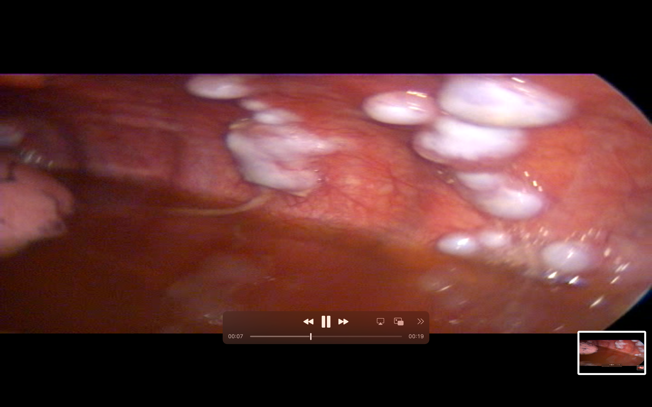

Under short GA, Diagnostic Thoracoscopy was done through left 5th ICS Mid axillary Line. Large white colored multiple pleural nodules were found deposited on the parietal pleura.

Fig 2

Final Diagnosis – Metastatic AdenoCarcinoma

Figure 2